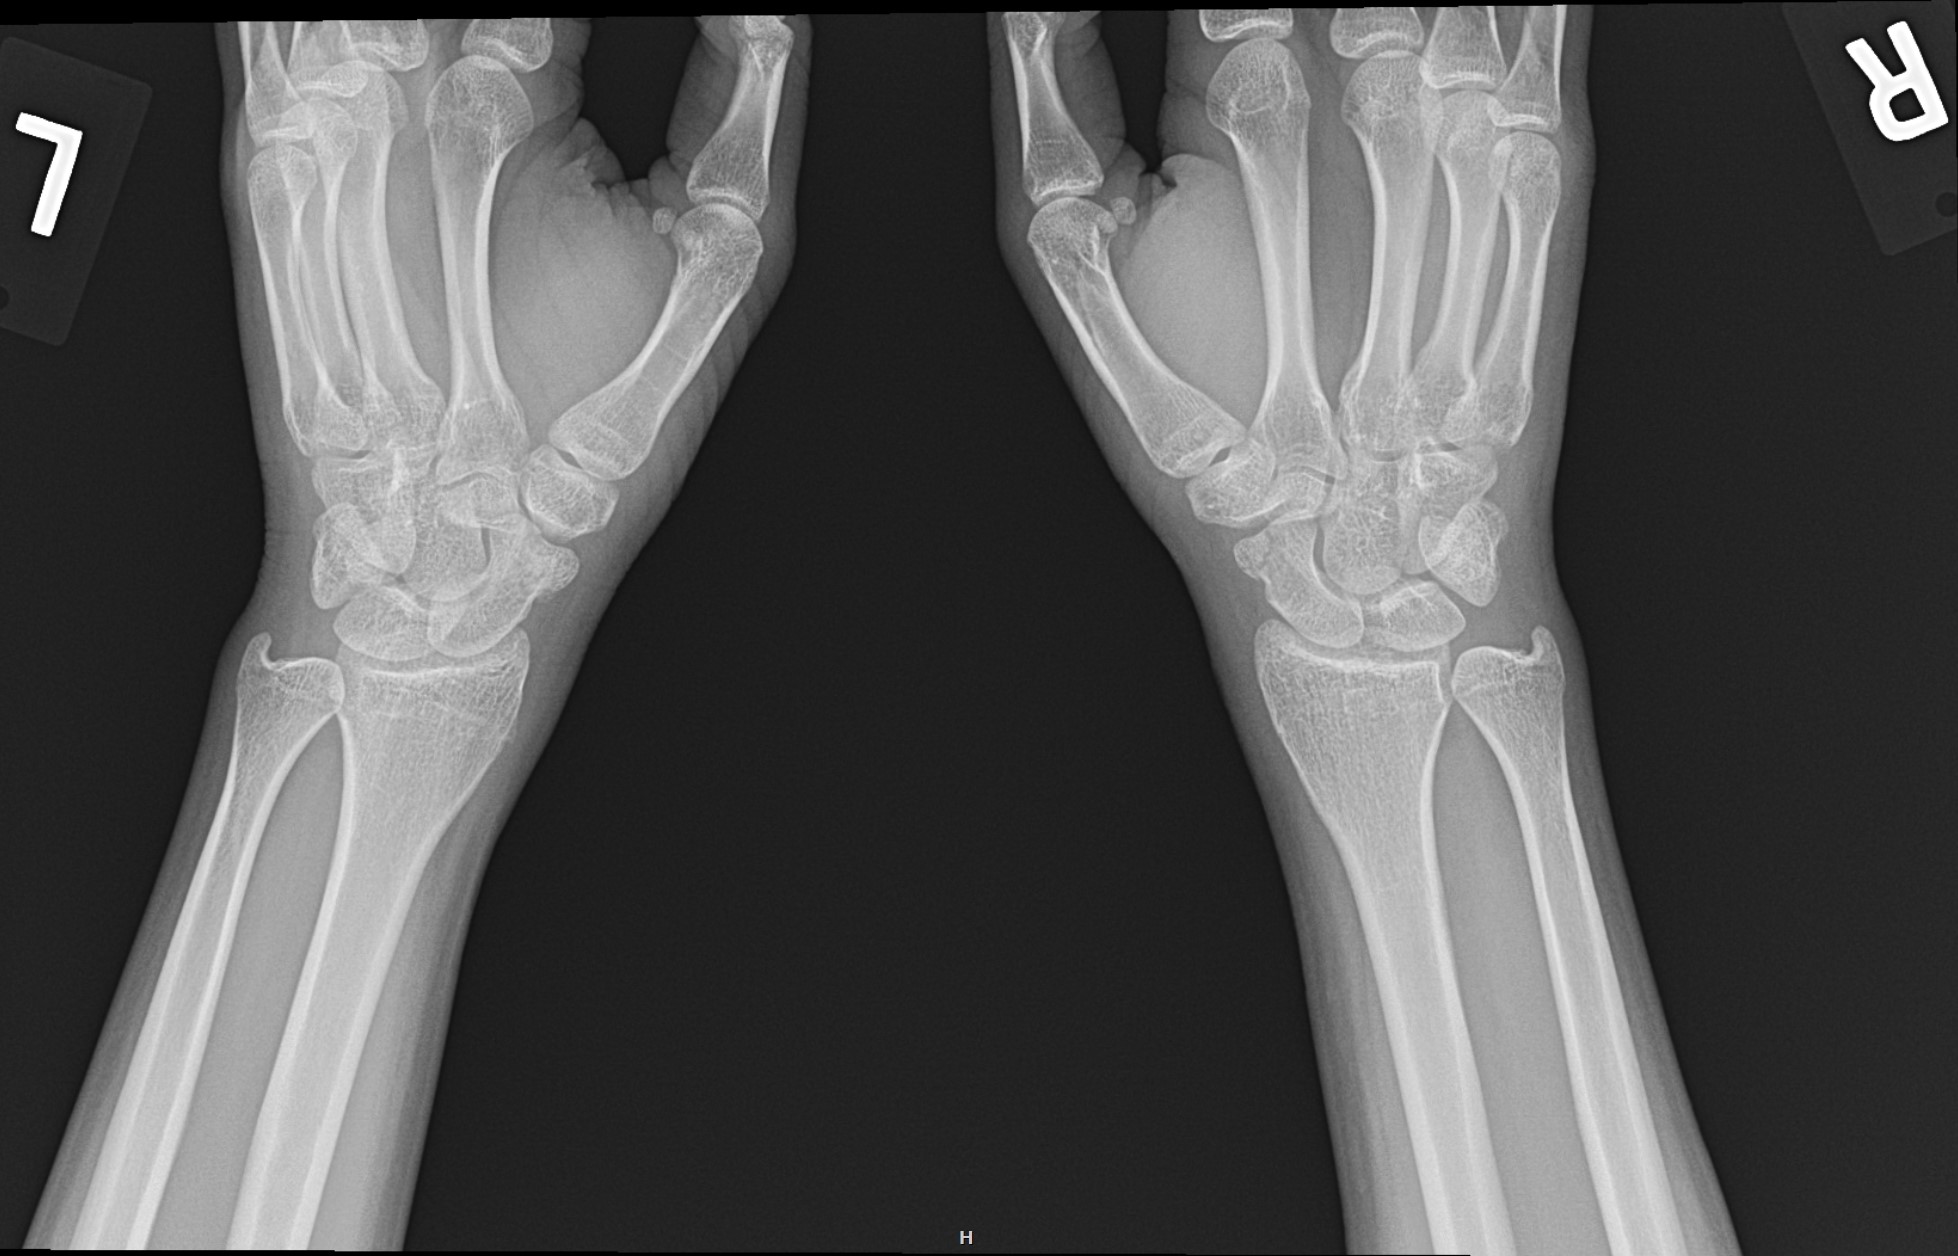

gout arthritis ( rid3567 )